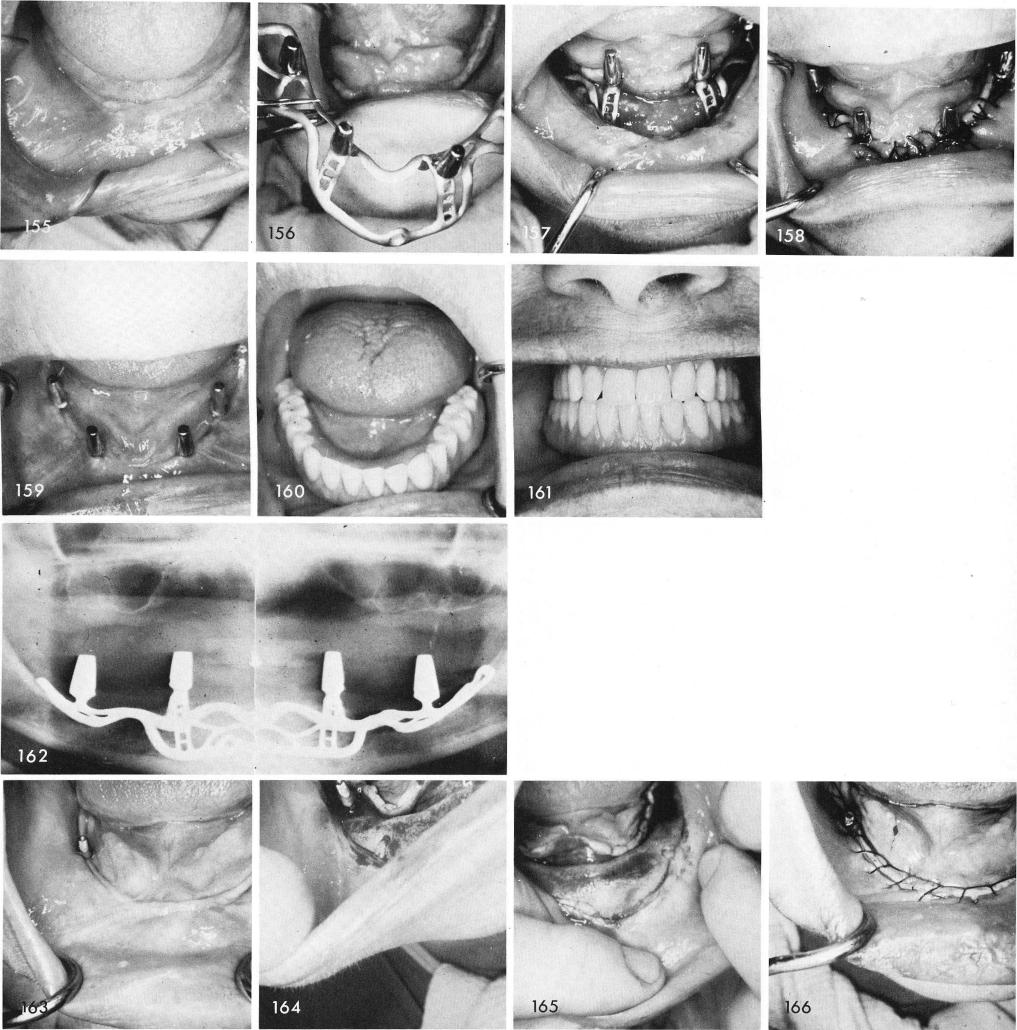

This next case, fig. 155, was designed with fenestrated secondary struts and solid primary struts, figs. 156, 157, 158, 159, 160, 161, 162.

A remaining blade post firmly anchored into the bone existed in this otherwise totally edentulous mandible, fig. 163. The bone was exposed revealing the mental foramina on both sides, figs. 164, 165, and after the impression which included the existing blade post, the tissues were sutured closed, fig. 166. The casting framework included a coping that would be cemented

1 Exposure of mandibular bone revealing mental foramina